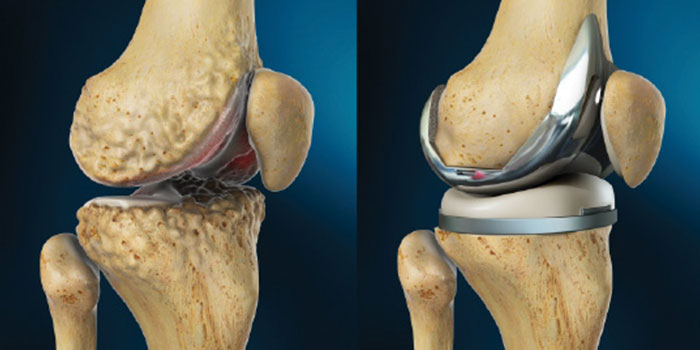

Total knee replacement, also called total knee arthroplasty, is a surgical procedure in which the worn out or damaged surfaces of the knee joint are removed and replaced with an artificial prosthesis.